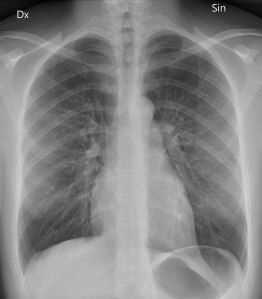

Chest X-Ray Coloration

Normal Chest X-Ray. This image shows a normal chest. Darker colors indicate less dense material, and lighter colors indicate more dense material. The lungs appear black because they are spongy with a lot of air content. The bones appear white because they are hard, mineralized, and block x-rays effectively.